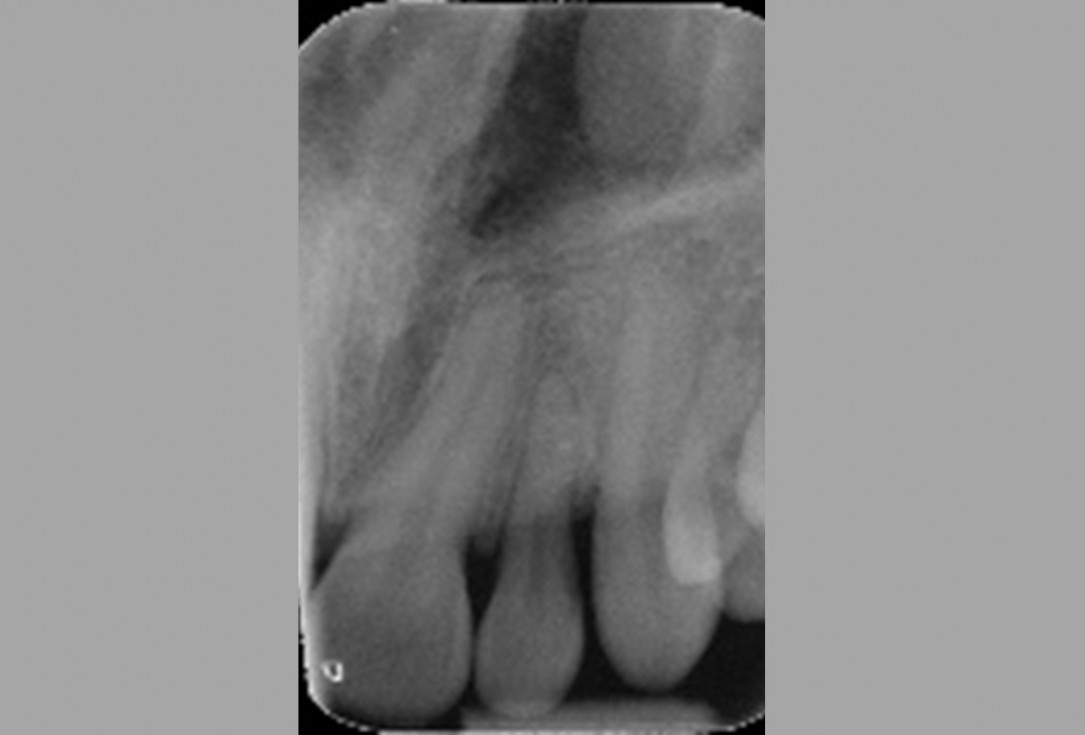

01/11 - Pre-operative radiographic view. Intrabony defect on the distal aspect of the lateral incisor.Non-contained intrabony defect treated with the modified papilla preservation flap in conjunction with cerabone® and Straumann® Emdogain® - Dr. J. Tunkel